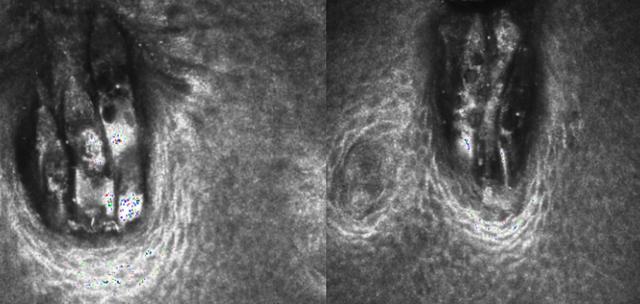

此两图均为睫毛毛囊处的螨虫,体长仅0.1~0.4毫米,身体呈椭圆形,相对细长,有4对足,尾部较长,末端顿圆,呈指状。

睫毛上的螨虫主要为蠕形螨,体长仅0.1~0.4毫米,肉眼无法看见,共焦生物显微镜放大800倍,可以清楚的看到螨虫,临床上主要分为两种:毛囊蠕形螨寄居于毛囊深处,以上皮细胞为食;皮脂蠕形螨栖息在皮脂腺与睑板腺内,以皮脂为营养。

正常情况下蠕形螨可与人体共生,一旦数量失控或免疫力下降,便会引发蠕形螨睑缘炎,加重眼干、眼痒与睫毛脱落,这些细微病变均可通过活体共焦显微镜清晰识别。